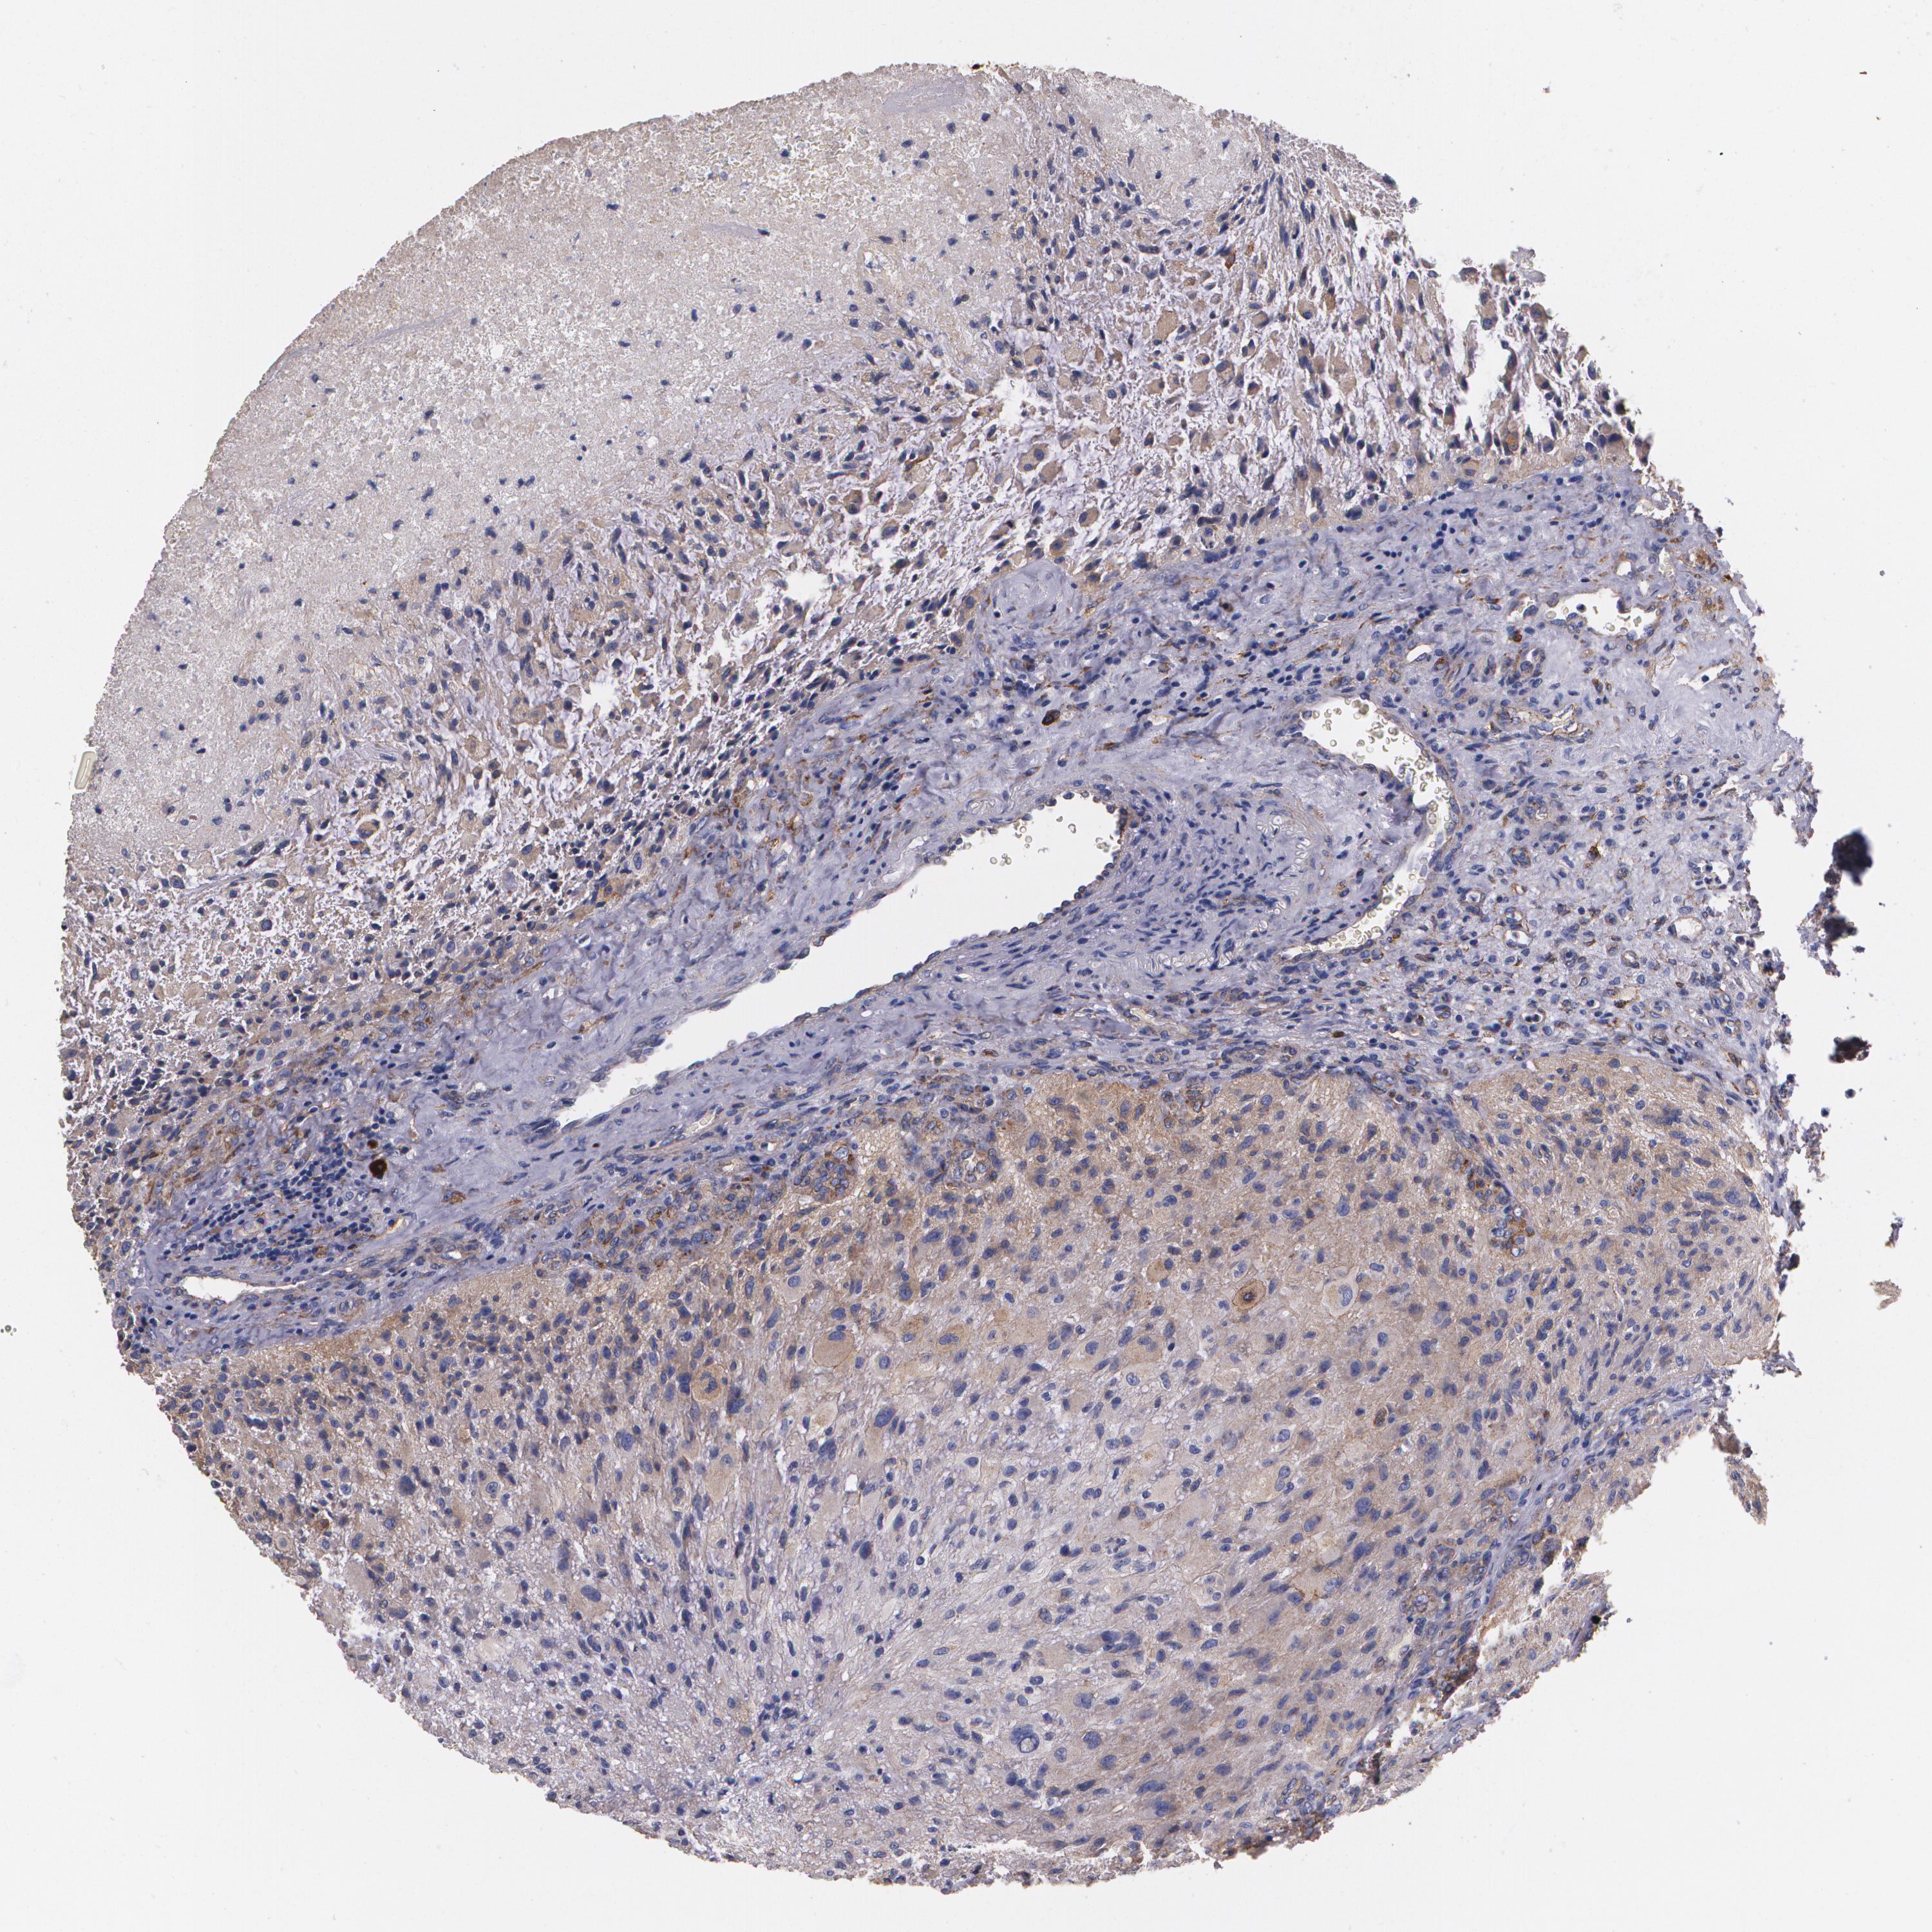

GLIOMA - Protein expressioni

A mouse-over function shows sample information and annotation data. Click on an image to view it in a full screen mode. Samples can be filtered based on level of antibody staining by selecting one or several of the following categories: high, medium, low and not detected. The assay and annotation is described here.

Note that samples used for immunohistochemistry by the Human Protein Atlas do not correspond to samples in the TCGA dataset.

Antibody stainingi

Antibody staining in the annotated cell types in the current human tissue is reported as not detected, low, medium, or high, based on conventional immunohistochemistry profiling in selected tissues. This score is based on the combination of the staining intensity and fraction of stained cells.

Each image is clickable and will lead to virtual microscopy that enables deeper exploration of all samples and also displays staining intensity scores, fraction scores and subcellular localization as well as patient and tissue information for each sample.

Antibody HPA001636

Antibody HPA001637

Antibody CAB010822

Staining

High

Medium

Low

Not detected

Intensity

Strong

Moderate

Weak

Negative

Quantity

>75%

75%-25%

<25%

None

Location

Nuclear

Cytoplasmic/membranous

Cytoplasmic/membranous,nuclear

Glioma, malignant, High grade

Glioma, malignant, Low grade

Glioma, malignant, NOS